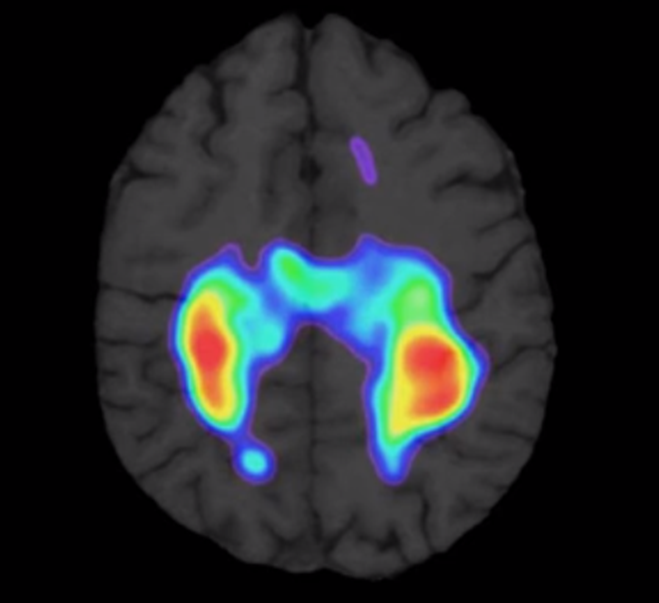

.以上是使用Brainpaths® 時真實的腦部掃描, 紅色和黃色清楚顯示我們腦部的運作

.我們可清楚看見腦部的運作的地方和體感皮質(somatosensory cortex) 及運動皮質(motor cortex)重疊